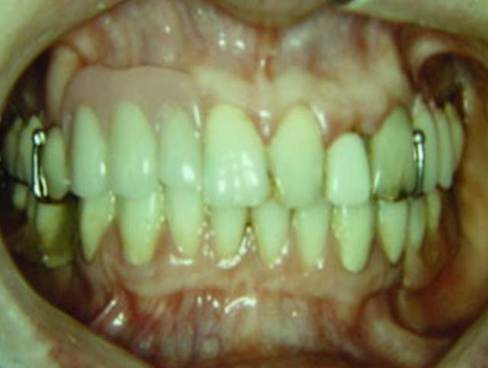

そして、完成です。

ドイツで、35年前、Körber教授の指導の下、初めてのリーゲルテレスコープ症例を 行った私の思い出の症例です。

その後、日本に紹介させていただき、30年以上経過しましたが、私は、当時Körber教授20年症例をいつのまにか超える結果をだすことができました。